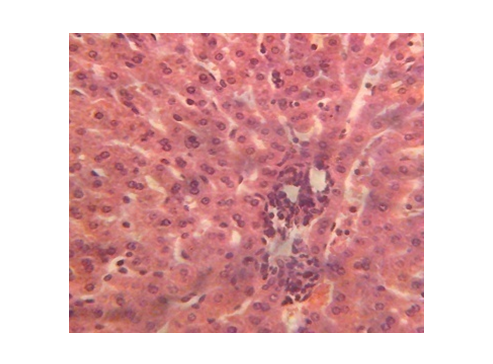

Figure 4 Kidney micrograph of control rat showing normal glomerular(G) structure at 3 and 5 weeks. (H & E stain X400).

The results of this study however disagree with the results of Jianpu et al.56 who reported that serum ALT and AST levels in diabetic rabbits were within normal ranges and Gidado et al.21 who reported insignificant changes in serum levels of ALT and AST in diabetic rats. The liver is one of the tissues that bear the brunt of chronic hyperglycaemia, since glucose is freely permeable to its cells Meyes.57 This unrestrained entry, in the presence of excess and sustained glucose in the blood is bound to cause metabolic derangements which would express themselves on the gross architecture of the tissues Atangwho et al.58 Present observations on the diabetic rat kidneys showed a progressive damage which increased with duration and severity of hyperglycemia as recorded by Muhammad et al.59 the resultant renal damage was caused by severe hyperglycemia induced by alloxan. There were septal haemorrhages, glomerular degeneration, increased capsular space with tubular epithelial damage and dysplasia as observed in kidney sections of the diabetic rats. These findings are in agreement with the findings of Kim et al.;60 Muhammad et al.;59 Renno et al.61 who showed tubular epithelial changes and enlargement of lining of cells of the tubules (Figures 5‒11).

The structural changes in the kidneys could be attributed to altered metabolism in diabetes Rasch,62 and subsequent effects on the increased renal threshold for hyperglycemia.29 Moreover, glucose overload damages the mesangial cells in the renal glomerulus through oxidative stress Brownlee.63 In the diabetic kidney, enhanced glucose uptake occurs in many cell populations including glomerular epithelial cells, mesangial cells and proximal tubular epithelial cells leading to the excessive production of intracellular ROS, making these cells particularly susceptible to diabetic milieu Forbes et al.;64 Eze,65 reported some degeneration of glomeruli with presence of tubular casts and signs of chronic inflammation in diabetic wistar rats. Peter et al.66 had previously reported a damaging effect of diabetes in the glomerulus, thereby affecting Glomerular Filtration Rate (GFR). Zafar et al.67 also reported that streptozotocin-induced diabetic rats showed some functional and morphological changes in the kidney. These morphological abnormalities in the kidney of diabetic rats were associated with significant elevations in serum urea and creatinine levels, indicating impaired renal function of the diabetic animals. The results are consistent with those of Shah et al.68 who reported elevated serum urea and creatinine levels as a result of renal damage in diabetic rats. The histological sections of the hearts of diabetic as well as non-diabetic rats showed normal architecture of the myocardium for the study period. This is consistent with the work done by Kita et al.69 who reported short-term metabolic disorders in diabetic rat heart with histopathological changes occurring later. The results disagree with those of Komolafe et al.24 who reported architectural alterations in myocardium and microanatomy of cardiovascular structures of diabetic animals. In the present study, serum lipid profile was used to assess the risk of development of cardiovascular disease which recorded elevated total cholesterol, LDL-C, VLDL-C and triglyceride levels whereas HDL-C levels decreased in alloxan-induced diabetic rats which is associated with cardiovascular diseases as seen in diabetes. The abnormal high levels of serum lipids in diabetes is mainly due to increased activity of hormone sensitive lipase in insulin deficiency resulting in enhanced lipolysis and mobilization of free fatty acids from the peripheral depots and adipose due to underutilization of glucose. Some of the excess fatty acid produced is then metabolized to acetyl coA which is used in the synthesis of cholesterol in the liver, thus increasing cholesterol levels in diabetes. On the other hand, glucagon, catecholamines and other hormones may also enhance lipolysis. Therefore, the uninhibited action of lipolytic hormones on the fat depots may be responsible for this increase. The lack of insulin and elevations of counter regulatory hormones lead to activation of enzyme (hormone-sensitive lipase) that stimulate lipolysis and enhance release of free fatty acids from adipose tissue. The fatty acids from adipose tissues are mobilized for energy purpose, and excess fatty acids are accumulated in the liver, which are converted to triglycerides Suryawanshi et al.70 The high levels of LDL-C may be attributed to diminished levels of LDL receptors resulting in increased circulating LDL particles Suryawanshi et al.70 The decreased serum HDL-C levels in the present study may enhance CVD risk since HDL-C function is to remove cholesterol atheromas within arteries and transport them back to the liver for excretion and re-utilization. The results support the works of21,23,24,40,68 who reported marked increase in cholesterol, triglycerides, LDL-C, VLDL-C and decreased HDL-C in diabetic rats when compared to non-diabetic rats. However, Jos et al.71 reported no correlation between diabetes mellitus and lipids in the study conducted with diabetes patients.